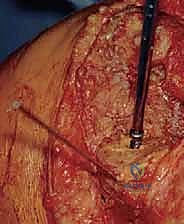

الخطوة الأولى: الشق الجراحي والوصول للمفصل

يستخدم الدكتور هطيف الشق الجراحي القديم غالباً، مع تمديده إذا لزم الأمر. يتم فتح الأنسجة بعناية فائقة، حيث تكون الأنسجة متليفة ومندبة من الجراحة السابقة. يتم حماية الأوعية الدموية والأعصاب بدقة باستخدام تقنيات الجراحة الميكروسكوبية إذا لزم الأمر.

الخطوة الثانية: إزالة المفصل القديم بأمان

هذه من أدق الخطوات. يجب إزالة المكونات المعدنية القديمة والإسمنت العظمي دون كسر العظم المتبقي الرقيق. يستخدم الدكتور هطيف أدوات متخصصة مثل المناشير الرفيعة والأزاميل الدقيقة لفصل الإسمنت عن العظم بأقل قدر من الخسائر العظمية.